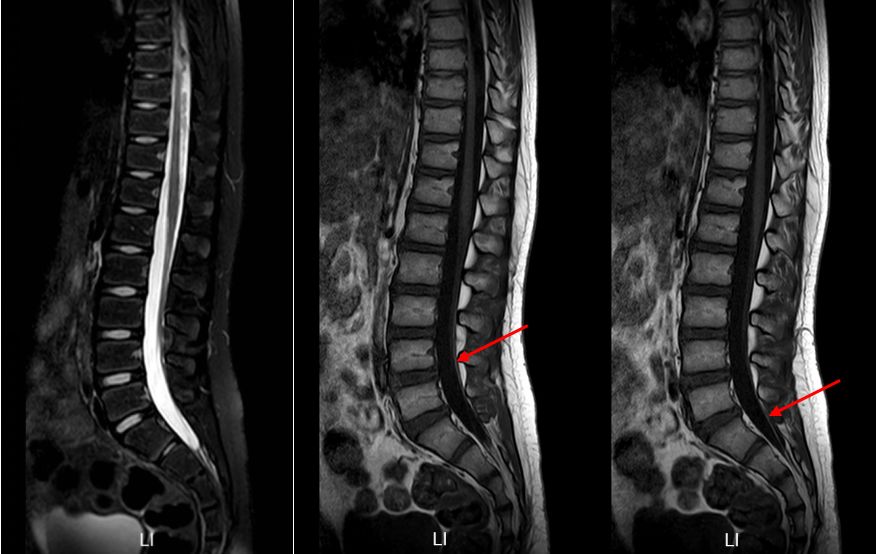

再次入院后予完善相关检查,相关病毒检测均提示阴性,炎症指标不明显。请神经外科会诊:结合患儿有下肢乏力,行走不稳,腰背部及双下肢疼痛,小便困难,大便失禁及便秘等症状,需排除存在脊髓栓系可能。回顾阅片初次的腰骶髓MR(图1):可见膀胱充盈扩张明显,横断面似见终丝脂肪浸润,建议再次复查MRI,可见终丝脂肪信号(图3)。

图3. 腰骶髓MR:箭头所指处可见终丝脂肪信号,T1上高信号,T2上低信号。

请放射科等多学科MDT讨论后认为:脊髓圆锥末端位于L1下缘水平,腰膨大形态较僵,终丝处于绷紧状态,位置偏后,横断面T2上终丝信号偏低,脂肪浸润可能,需考虑脊髓栓系综合征。